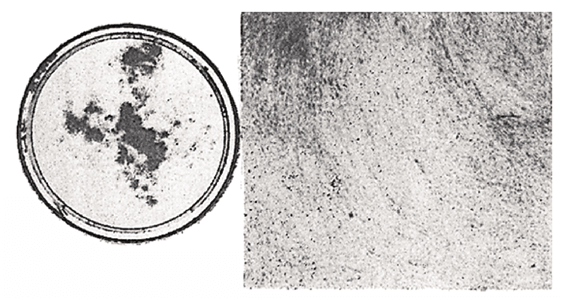

1. SV40 cancer virus (DNA virus type) transformation experiments were performed on mouse kidney cells.23 An intervention experiment with the addition of SA (35μg) showed that the expression of carcinogenesis was generally reversible. SV40 virus (106PFU) transformation experiments were performed using SA (35μg) on mouse kidney cell (103/dish). Upper panel: SV40 (106PFU) virus only (Figure 14). Lower panel: SV40 (106 PFU) + SA (35μg) (Figure 15).

2. Microscopic observations of the black sites under high magnification showed that SA prevented carcinogenesis by inhibiting cell to cell contact ( as shown in the next photograph) despite the large exposure of SV40 virus( 106PFU/0.2ml) to mouse kidney cells(103/dish) (Figure 16).

3. In the plate on the right side of the photograph, the cell contact inhibition is clearly shown after the addition of SA (35μg). The left side photo shows the aggregation of cells, which is clearly transformed (Figure 16).

Figure 14 Inhibiting effect of SA on SV40-transformation of mouse cells without SA.C3H mouse kidney cells (103) were seeded on one plate in the absence of 35μg/ml of SA and infected with SV40 virus ( 106PFU/0.2ml). Aggregation and pile up are observed.

Figure 15 Effect of SA on inhibiting SV40-transformation of mouse cells with SA. C3 H mouse kidney cells (103) were seeded on one plate in the presence of 35μg/ml of SA and infected with SV40 virus (106PFU/0.2ml). Black spot are there, but no transformation observed.

Figure 16 Microscopic observations of the black sites under high magnification. Mouse kidney cells (103) were seeded in the absence (left side) and presence (right side) of SA( 35μg/ml). SV40 virus (3.5 x 106PFU) was infected. They were grown up for 14 days. There is confirmatively cell to cell contact inhibition on the right side photograph in comparison with left side photograph which showed transformation and aggregation.